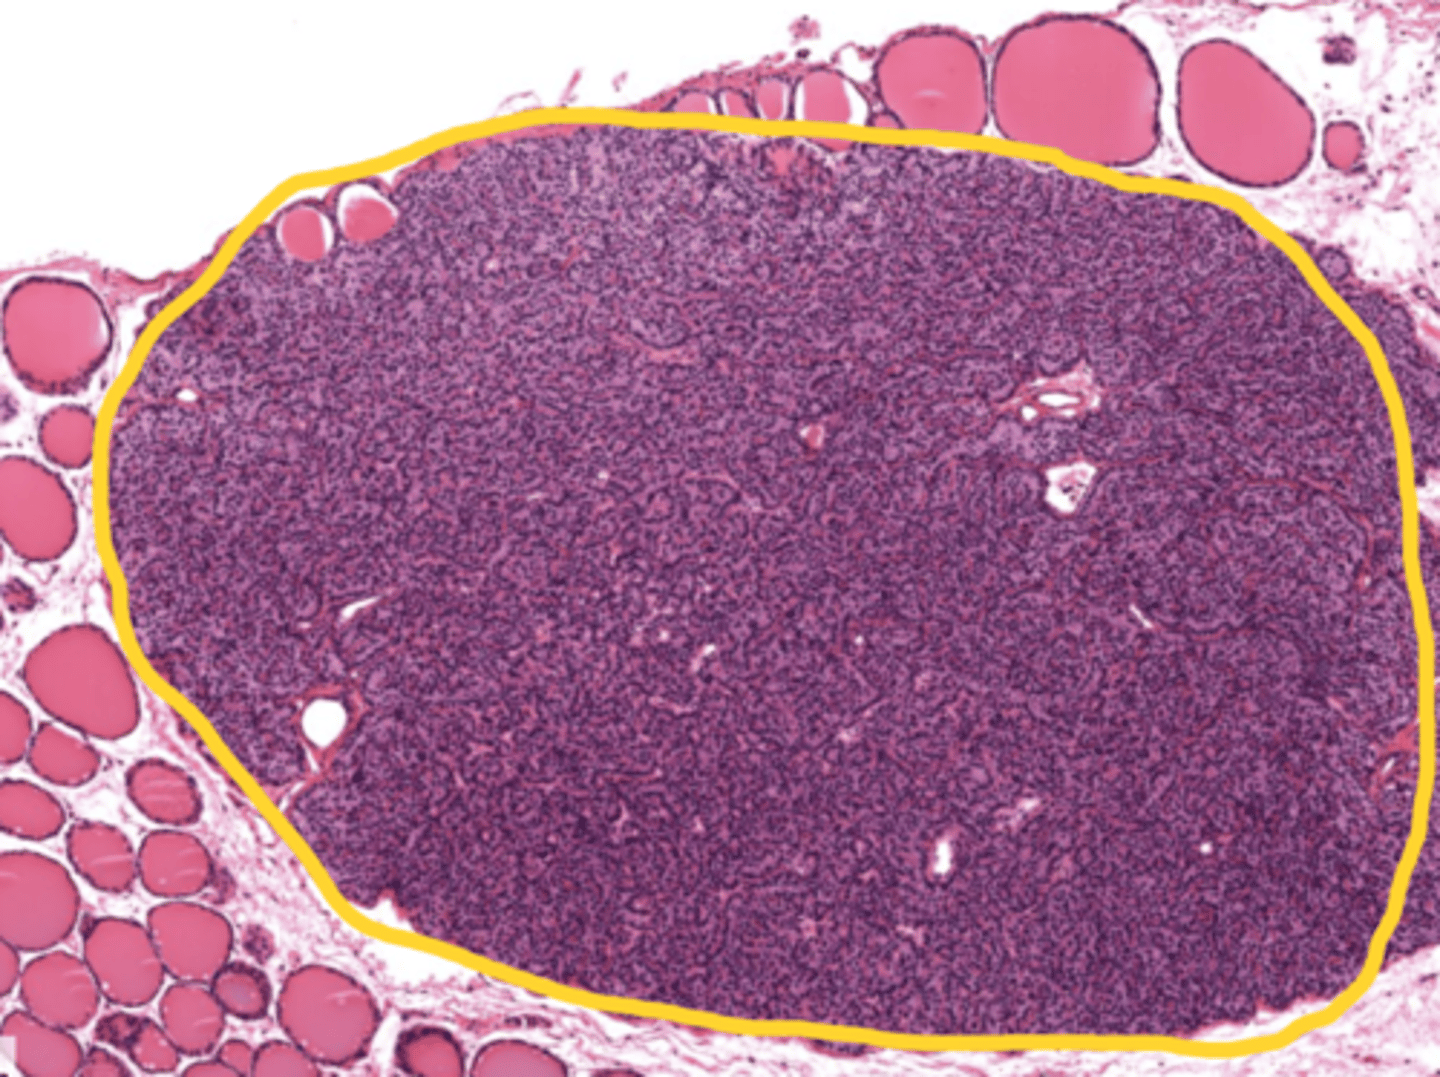

Thymus